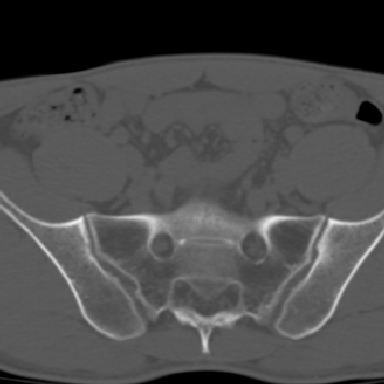

m 30 腰背部不适半年; 清晨时僵硬; 活动症状有所改善

双侧骶髂关节下2/3关节面模糊,毛糙,可见小囊状骨质破坏区.支持强直性脊柱炎.

强直性脊柱炎的早期改变!不仅表现为双侧骶髂关节,第5腰椎与骶椎间的关节突关节也有类似改变。

双侧骶髂关节下2/3关节面模糊,毛糙,髂骨侧可见小囊状骨质破坏区,骶髂关节间隙增宽(软骨破坏期)。支持早期强直性脊柱炎。

双侧骶髂关节下2/3关节面模糊、毛糙,可见小囊状骨质破坏区,呈虫咬状改变,周围可见增生硬化.支持强直性脊柱炎早期表现.

双侧骶髂关节髂骨面硬化,毛糙,小囊变,属于早期强直性脊柱炎